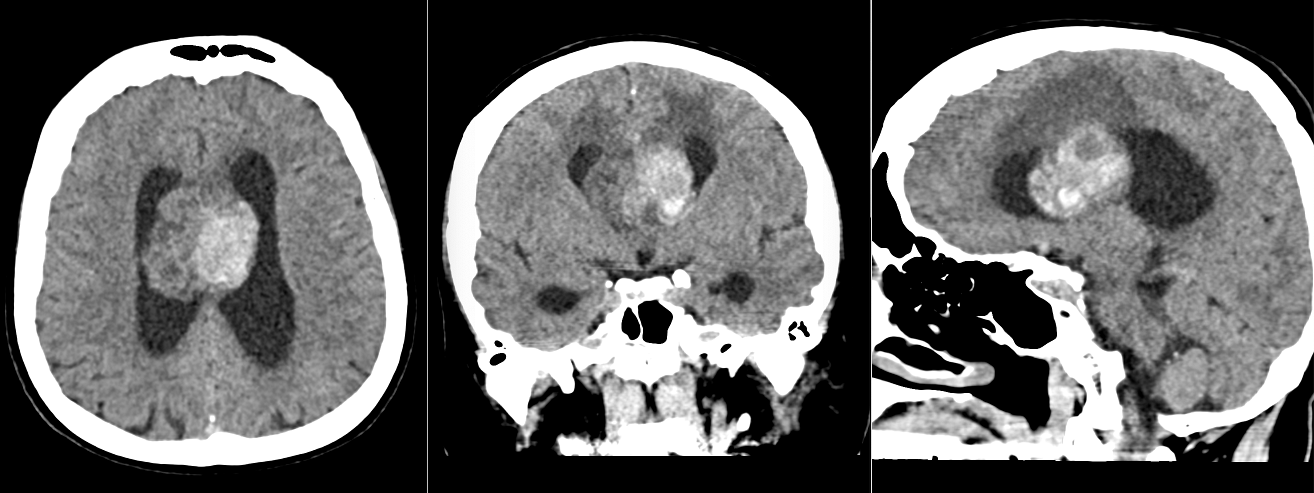

Imagistică – o tumoră „care se arată”

RMN-ul este, de cele mai multe ori, sugestiv:

- localizare intraventriculară, atașată de septul pellucid sau peretele ventricular

- aspect lobulat, uneori polilobat

- zone chistice și calcificări

- captare heterogenă de contrast

Pe CT, calcificările pot fi evidente și ajută la orientarea diagnosticului.